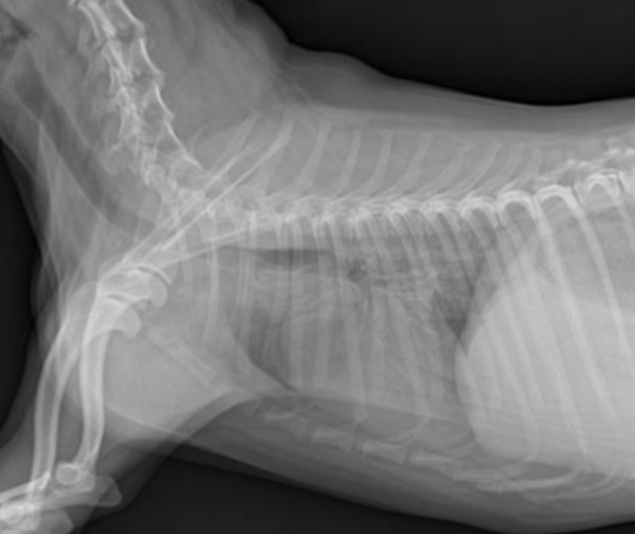

2. ํ๋ถ ๋ฐฉ์ฌ์ ํ๋ ์ ์ฃผ์ ํฌ์ธํธ

- ๊ฐ๋น๊ฐ ์์ชฝ์ผ๋ก ๊ฒน์น๊ฒ ์ฐ์ด์ผ ํจ.

- ํ๋ถ๋ ํก๊ธฐ์ ์ฐ์ด์ผ ํจ. (์๋๋ฉด ํก๊ฒฉ๋ง๊ณผ ์ฌ์ฅ์ด ๊ฒน์น ์ ์์.)

- ๋ณต๋ถ๋ ํธ๊ธฐ์ ์ดฌ์.